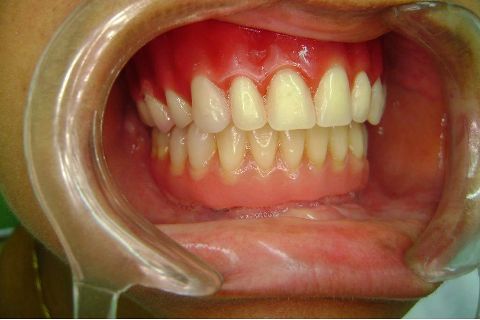

Atualização do caso clínico que já postei, "REABILITAÇÃO EM MAXILA ATRÓFICA COM IMPLANTES", um caso que inclui expansão do rebordo estreito com cinzel e martelo, expansores rosqueáveis, enxerto e instalação dos implantes distais inclinados tangenciando seio maxilar. Inclui esvaziamento do forame nasopalatino e preenchimento com biomaterial para instalação de dois implantes próximos dele. Cirurgia realizada em única sessão, com instalação dos 6 implantes. Para os colegas que não conheceram e/ou esqueceram da apresentação, este é o resumo do caso na fase cirúrgica.http://www.youtube.com/watch?v=BtvexFexRPA&hd=1

FASE PROTÉTICA DA REABILITAÇÃO EM MAXILA ATRÓFICA...incluindo a reabertura, instalação dos minipilares e PTR provisória reembasada sobre os cilindros de proteção.